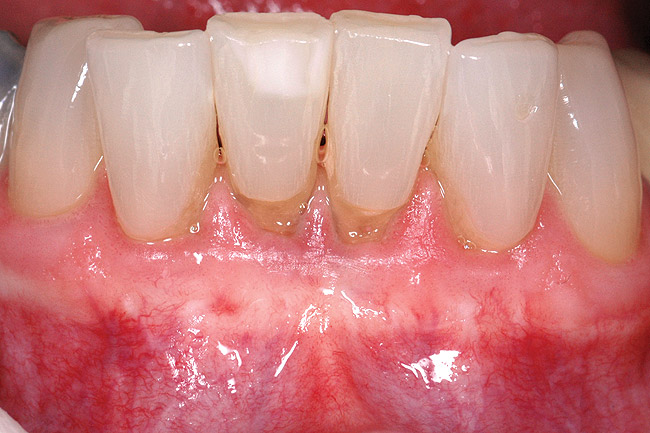

Fig 1 and Fig 2. Non-carious cervical lesion on the root surface of a maxillary canine. There was no attached gingiva, the cervical lesion was less than 2 mm in depth, and the recession was Miller Class I.

Figure 1